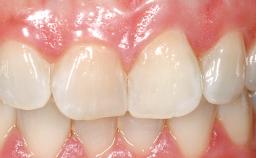

Immediate Placement of an Implant in a Maxillary Left Central Incisor Site

A 33-year-old female patient presented with an upper left central incisor that required extraction after a failed endodontic therapy. The tooth had been traumatized when the patient was a teenager and had undergone several endodontic treatments, including two apicectomy procedures. The patient was in good health and did not smoke. Clinical examination showed that the patient had a high lip line. In full smile, the gingival margins of the upper teeth were visible to the first molars. The gingival margins of central incisors 11 and 21 were only just showing. Examination of tooth 21 confirmed that the tooth was mobile and had hypererupted by 1 mm.

Prosthesis Type FDP

Lip Line No exposure of papillae Exposure of papillae Full exposure of mucosa margin